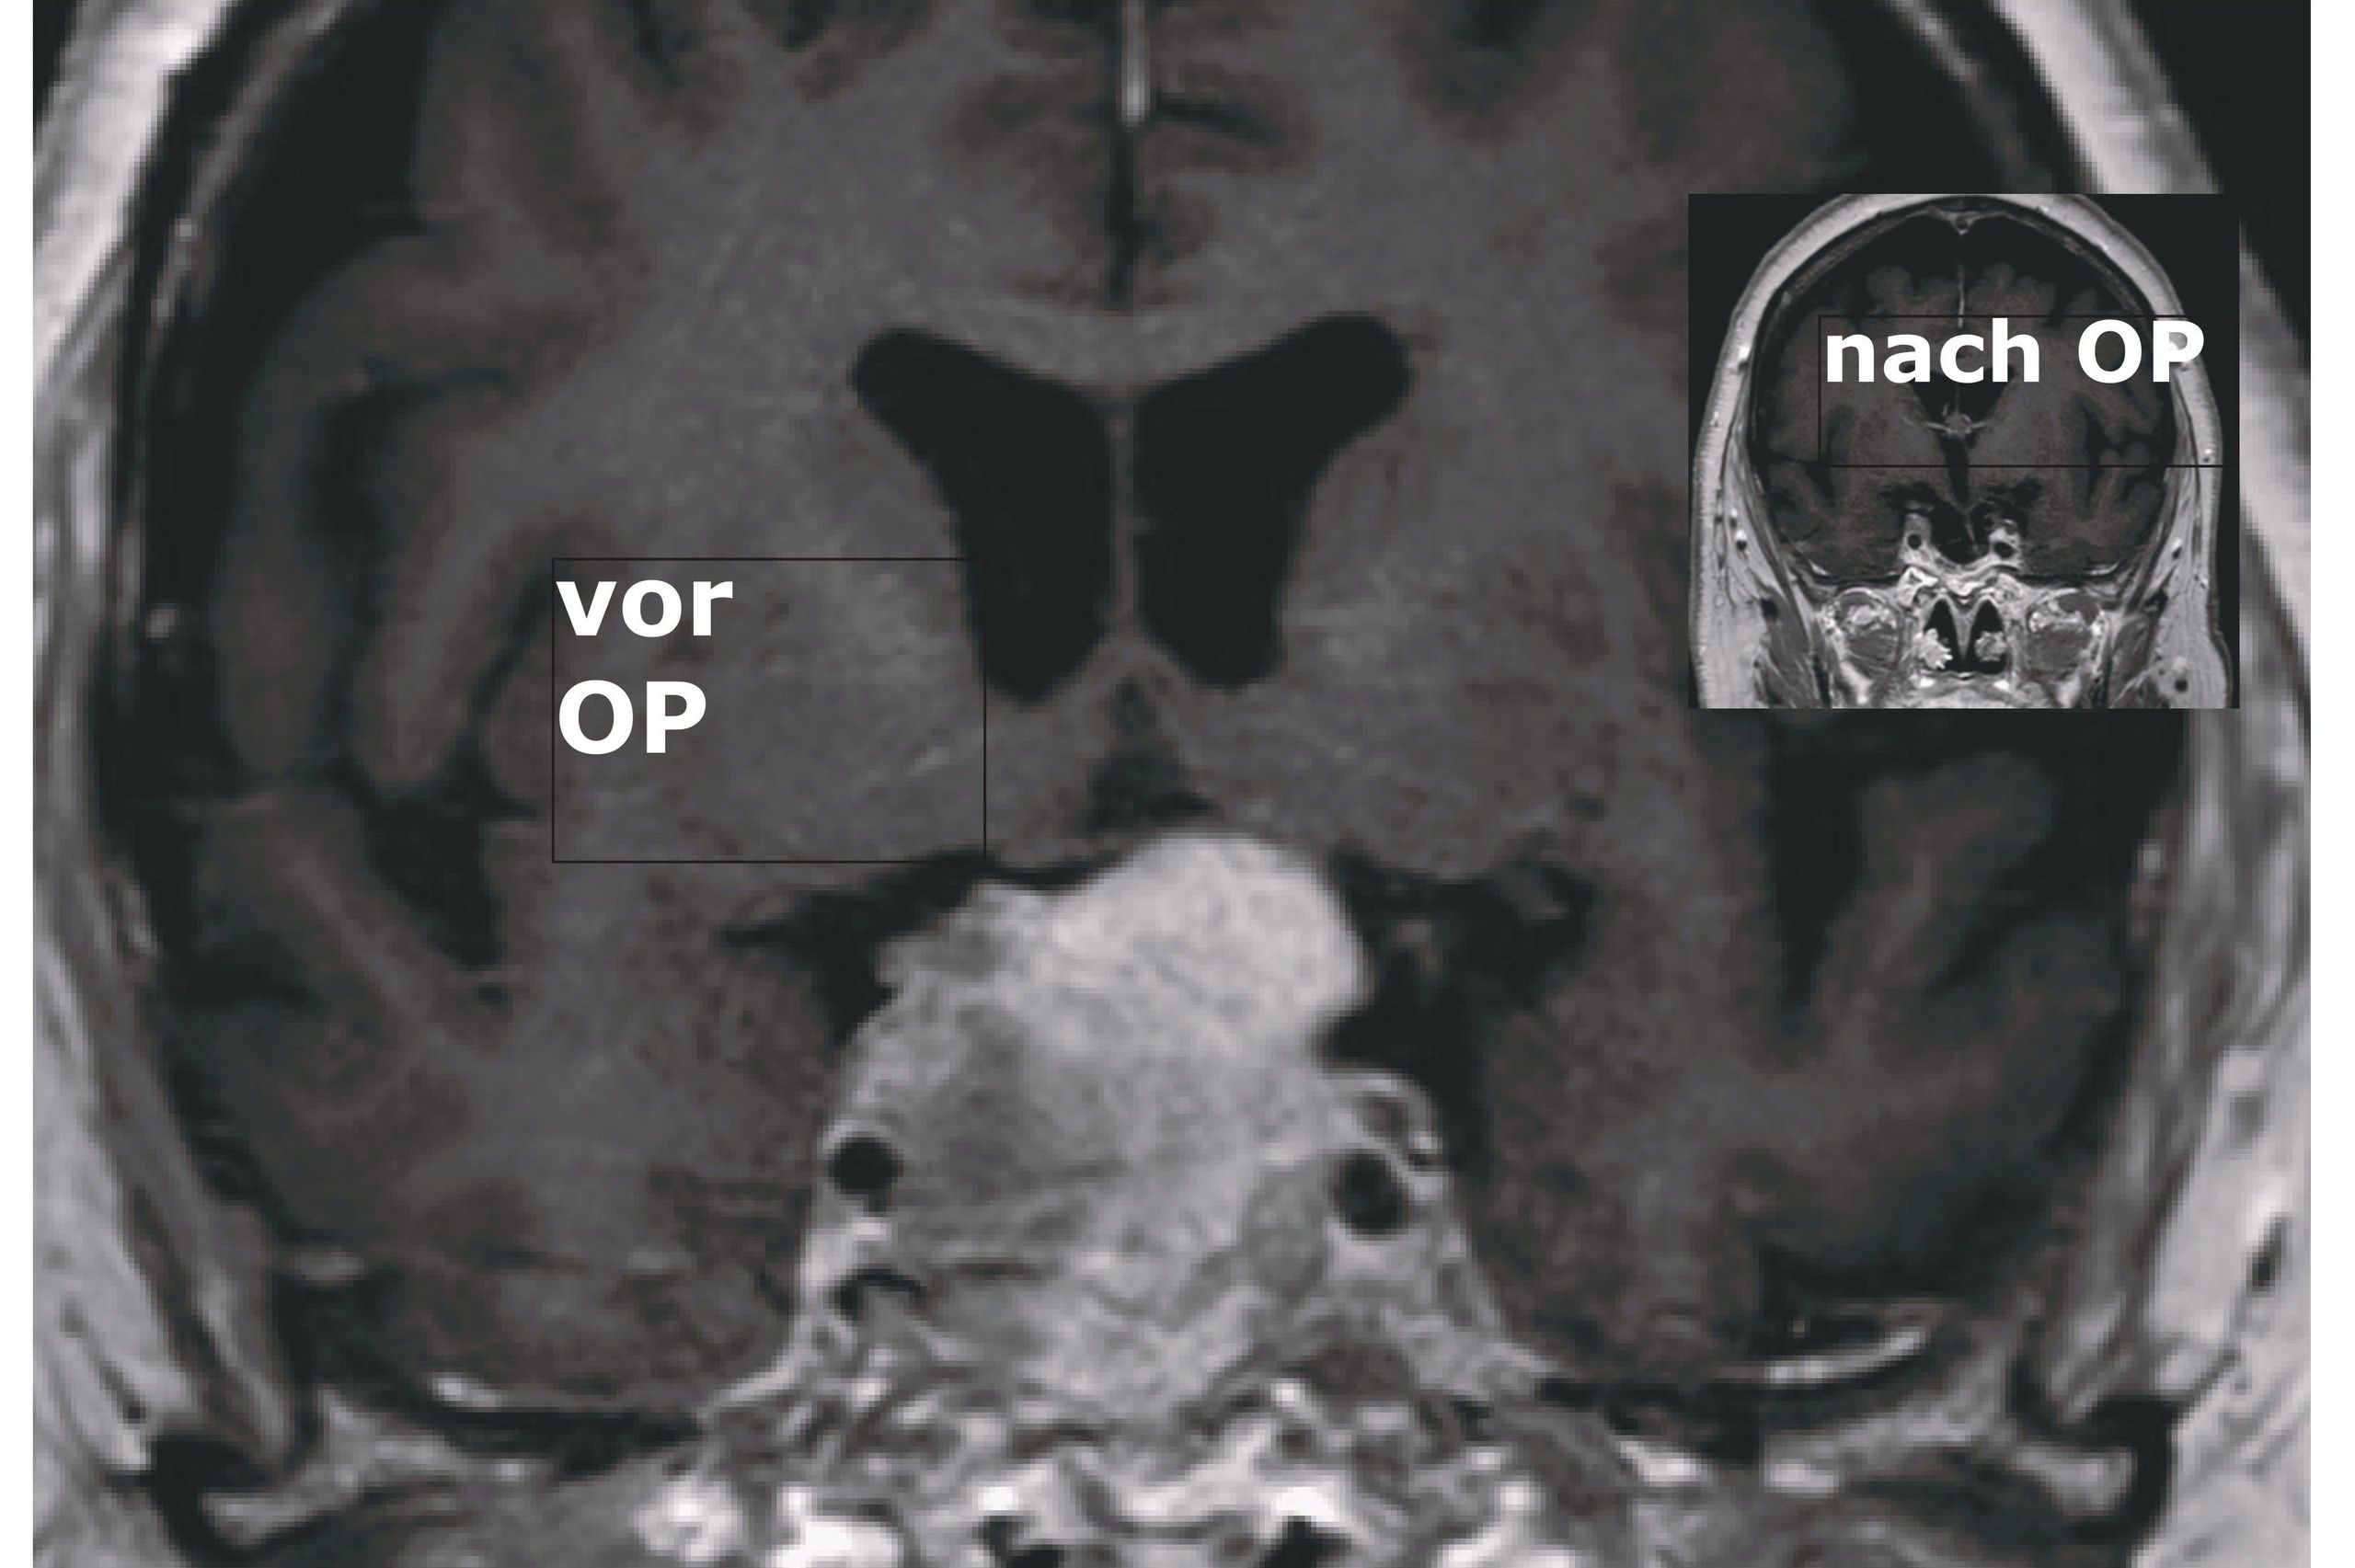

Ist die Erkrankung durch eine MRT-Untersuchung eindeutig diagnostiziert, wird das Adenom in der Regel durch die Nase endoskopisch entfernt. „Die Patienten bleiben nach der OP lebenslang unter Kontrolle, aber nur in ganz seltenen Fällen kommt der Tumor wieder“, erklärt PD Dr. med. habil. Michael Fritsch, Chefarzt der Klinik für Neurochirurgie. Über die interdisziplinäre Diagnostik und Therapie des Hypophysenadenoms spricht er beim Gesundheitsforum DBK am 23. März 2026 um 17 Uhr im Konferenzraum des Hauses G (Bethesda Klinik) in Neubrandenburg.